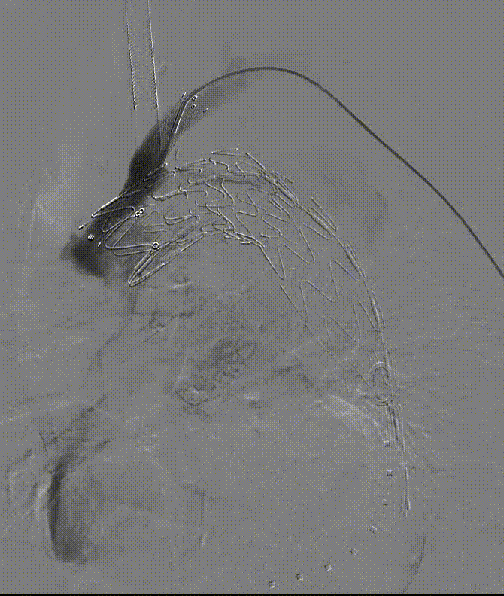

【病例3】B型夹层,TEVAR术后Ⅱ型内漏

复杂病例再干预方案:联合应用栓塞、覆膜支架及封堵器

术后四个月CTA

第二次术前造影,证实为LSA所致Ⅱ型内漏

LSA置入覆膜支架后造影,内漏消失